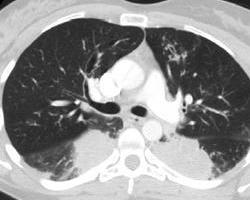

♥过敏性支气管肺曲霉病

过敏性支气管肺曲霉病[1](allergicbronchopulmonaryaspergillosis,ABPA)是过敏性支气管真菌病中最常见和最具特征性的一种疾病,1952年在英国首先报道。其致病曲霉以烟曲霉最常见,赫曲霉、稻曲霉(A.oryzae)、土曲霉偶可见到。